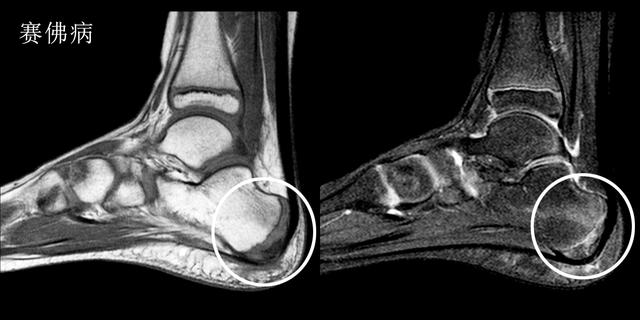

赛佛病---孩子也会得的跟痛症

足部是第一个成长为全尺寸的身体部位之一。这通常发生在青春期早期。在此期间骨骼通常比肌肉和肌腱生长得更快。结果肌肉和肌腱变得紧绷,使鞋跟区域变得不那么柔软。在承重活动期间,会伤到脚跟诱发疼痛导致塞弗病(Sever's Disease)。

赛佛病主要的症状是在运动时,尤其是跑跳时出现明显的足跟痛。

Sever病在8至10岁的身体活跃女孩中最常见。最常见的是10岁至12岁的身体活跃男孩。足球运动员和体操运动员经常得到塞弗病。任何跑步或跳跃活动的儿童也可能面临更大的风险。Sever's疾病很少发生在年龄较大的青少年身上,因为足跟的背部通常在15岁时完成。

这种疾病诊断主要还是依靠核磁检查,在核磁图像中我们可以看到明显的跟骨周边的无菌性严重表现,从而判断孩子是否得了赛佛病。

这种疾病的治疗以保守治疗为主,冰敷、休息以及外用药物可以得到很好地治疗效果。